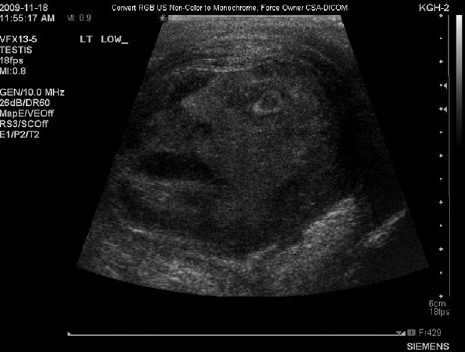

But when the scrotal ultrasound of a 45-year-old patient with severe testicular pain and a possible mass revealed the surprising image of a man in distress, urologists at Queen’s University, in Ontario, followed proper scholarly procedure: They submitted it to Urology, the official journal of the International Society of Urology.

“The residents and staff alike were amazed to see the outline of a man’s face staring up out of the image, his mouth agape as if the face seen on the ultrasound scan itself was also experiencing severe epididymo-orchitis,” wrote the authors, G. Gregory Roberts and Naji J. Touma, in an article that appeared in the journal’s September issue. “A brief debate ensued on whether the image could have been a sign from a deity (perhaps ‘Min,’ the Egyptian god of male virility); however, the consensus deemed it a mere coincidental occurrence rather than a divine proclamation.”